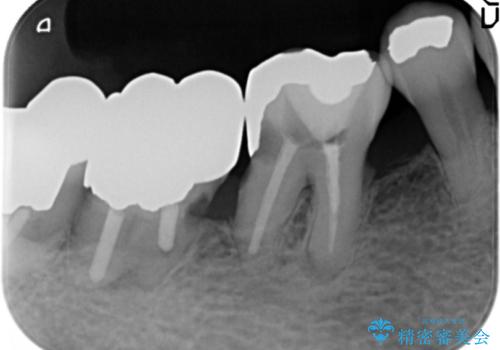

- 上の奥歯がないまま長年過ごしていたら前歯もぐらぐらしてきてしまったことを主訴に来院された患者様です。

奥歯の咬み合わせがないことにより前歯に負担がかかり動揺が出ていました。

精査したところ右下の奥歯も歯周病により保存不可能な状態でした。

なるべく予算を抑えたいとのご希望から、上顎は入れ歯、右下臼歯部はインプラントによる治療を行いました。

上の前歯は動揺を抑え、入れ歯の着脱にも耐えうるように被せ物を連結させることにしました。